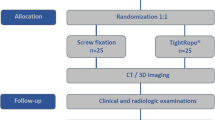

Experimental protocol and specimen allocation

(1)

Biomechanical tests were performed with all syndesmotic structures intact. These data was recorded as the intact group.

-

(2)

The ligaments of the syndesmosis were cut off, the 3D-printed template was used to make bone tunnels, and a suture-button was used to anatomically fix the syndesmosis. Afterwards, the same abovementioned biomechanical tests were performed, and these data were recorded as the anatomical model group.

-

(3)

With the lateral fibular bone tunnels unchanged, the fibula samples were moved anteriorly and posteriorly by 1 cm to establish the ant-malreduction and post-malreduction groups, respectively. Then, a 3D-printed guide plate was used to re-fix the specimens, in order to form the malreduction model (ant-malreduction and post-malreduction groups). Afterwards, the same biomechanical tests were performed, and data were collected as the ant-malreduction and post-malreduction groups. Figure 1 presents the experimental protocol, Fig. 2 shows the experimental setup, and Fig. 3 shows the CT scan of three bone tunnels made by template.